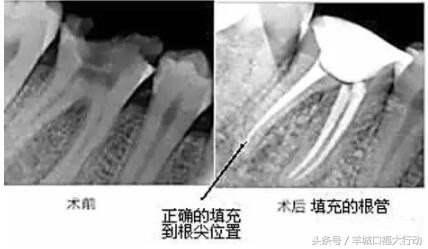

牙齿出现了疼痛,很多情况医生都会建议患者进行根管治疗,也就是老百姓常说的抽神经。其实很多人并不懂牙齿有洞出现了疼痛为什么不能直接补一下,而是非要选择抽神经。其实坦白的讲,如果牙齿出现了剧烈的疼痛,那么意味着患者已经错过了最佳的补牙治疗机会,那么最佳的治疗时机已经错过了,就不得不选择另一种治疗方案,也就是专业上讲到的根管治疗。

另外针对于磨牙来讲,通常磨牙会有3到4个牙根,但是牙根里面的神经可能会有多根,正常的磨牙根管治疗是指治疗3根神经的费用,如果这个牙齿的神经数量超过3根那么每多出来一根就要加收一根神经的费用。